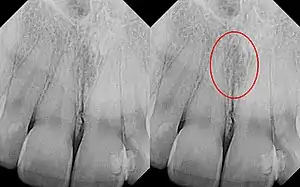

| Identical images with heart-shaped radiolucency highlighted in right film. | |

As a cyst, the nasopalatine duct cyst requires histological analysis for a definitive diagnosis. Radiographically, the nasopalatine cyst appears as a well-demarcated round, ovoid, or heart-shaped structure presenting in the midline of the maxilla.[6]